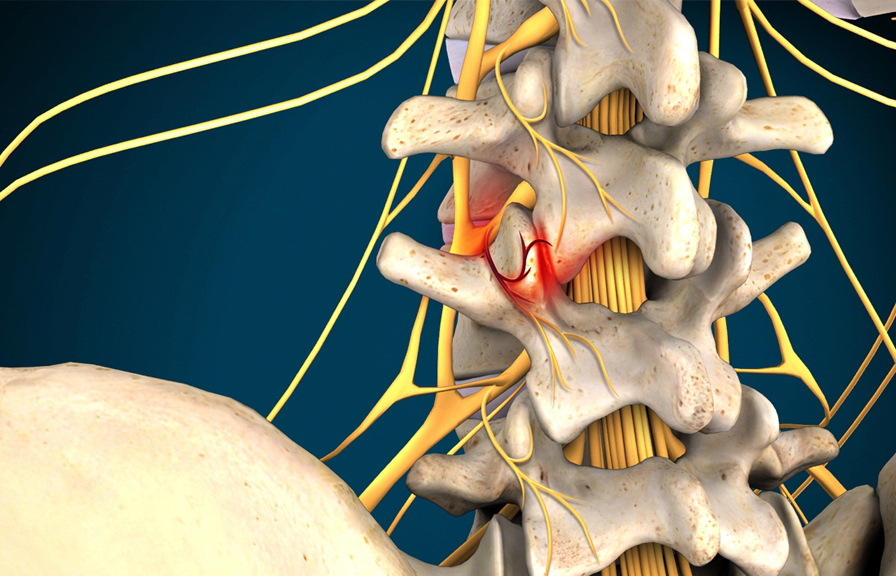

- Spinal Stenosis

- Pinched Nerves

- Sciatica